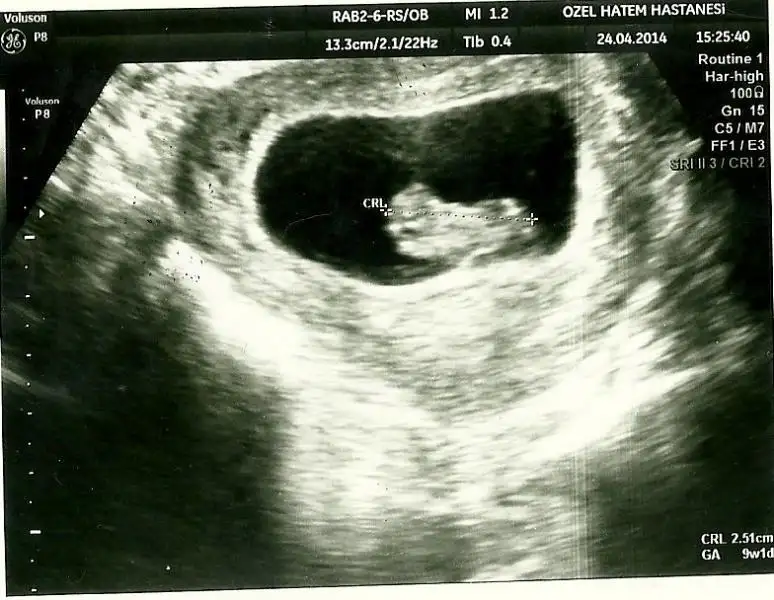

Eki Görüntüle 473829 bu bir erkek bebek genital nub cikintisi gayet yukarda